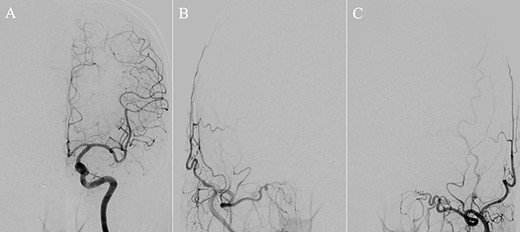

A patient in their 70s with extracranial lymphoma was incidentally found to have ACF–dAVF via head computed tomography and magnetic resonance angiography. Digital subtraction angiography (DSA) confirmed ACF–dAVF with multiple feeding branches, arising from bilateral OphAs, distal IMAs and the left middle meningeal artery (MMA), with cortical venous reflex (Borden type III, Cognard type IV) (Fig. 1). At the patient’s request, we chose endovascular, rather than surgical, treatment. We injected a 20% N-butyl-2-cyanoacrylate (NBCA)–lipiodol mixture into the fistula through bilateral ethmoidal arteries and the left MMA after we placed coils at the terminal branch of the right OphA. However, we could not achieve full penetration into the fistulous connections because of pressure secondary to high flow from the IMA branches, which resulted in incomplete obliteration (Fig. 1). Four months later, we repeated TAE by temporarily reducing nasal blood flow by inserting gauze infiltrated with xylocaine and epinephrine into the nasal cavities. After introducing the guiding catheter, an endonasal surgeon inserted X-ray-detectable surgical gauze infiltrated with 1% xylocaine and epinephrine (1:10 000) into bilateral nasal cavities using a nasal speculum, while paying full attention to avoid damage to the nasal mucosa. Then, we confirmed that the gauzes were placed in appropriate locations in the upper nasal cavity under fluoroscopic guidance. Immediately after insertion, we were able to confirm decreased blood flow from the IMA using DSA (Fig. 2). After this procedure, we navigated a DeFrictor Nano Catheter (Medico’s Hirata, Osaka, Japan) into the terminal branch of the OphA, which was connected to the dorsal nasal artery. Even though there was still a distance from the tip of the microcatheter to the shunt pouch, the NBCA reached the shunt point and penetrated the venous portion (Fig. 3). Follow-up DSA demonstrated complete obliteration of the ACF–dAVF, and blood flow in the nasal mucosa from the IMA branches recovered normally (Fig. 4).

Right (A) and left (B and C) internal carotid artery angiography before initial treatment showing ACF–dAVF with feeding arteries arising from branches of the OphAs; ethmoid artery (arrow) and dorsal nasal artery (arrowhead) (D and E). Bilateral external carotid artery angiography before initial treatment, anteroposterior view, showing the ACF–dAVF fed by bilateral distal internal maxillary arteries and the left middle meningeal artery.

(A) DSA, anteroposterior view, showing complete obliteration of the anterior cranial fossa–dural arteriovenous fistula. (B and C) DSA, anteroposterior view, showing restored blood flow from the internal maxillary artery branches.